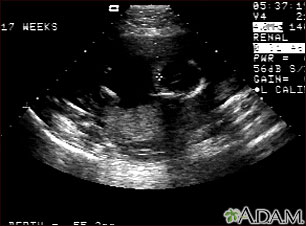

This is a normal fetal ultrasound performed at 17 weeks gestation. The development of the brain and nervous system begins early in fetal development. During an ultrasound, the technician usually looks for the presence of brain ventricles. Ventricles are spaces in the brain that are filled with fluid. In this early ultrasound, the ventricles can be seen as light lines extending through the skull, seen in the upper right side of the image. The cross hair is pointing to the front of the skull, and directly to the right, the lines of the ventricles are visible.